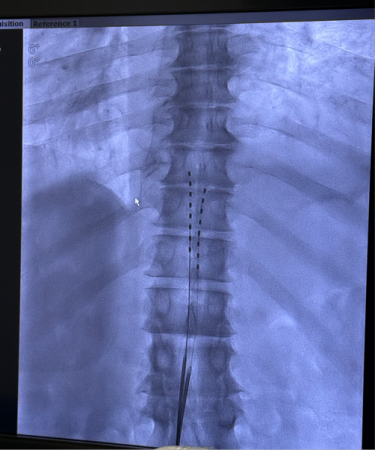

手术在DSA(数字减影血管造影)引导下开展,在肖红主任医师指导下,由银燕护师、卢帆助理研究员组成的手术团队精准将电极送达患者相应节段的硬膜外腔,并在术中完成刺激参数调试。T先生当场反馈,电刺激覆盖范围与疼痛区域高度重合,镇痛效果立竿见影,手术过程顺利完成。

from clipboard

电极植入到位